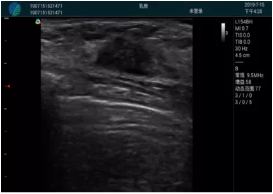

可視化穿刺引導(dǎo)

M20實(shí)時(shí)引導(dǎo):向包塊后方間隙注射利多卡因

清晰顯示腺體內(nèi)低回聲快影,邊界清晰,包膜較光滑

確定進(jìn)針路徑并實(shí)時(shí)監(jiān)測抽吸針與腫塊位置關(guān)系

抽吸針進(jìn)入腫塊內(nèi)部進(jìn)行旋切

抽吸過程中可見腫塊明顯縮小,并根據(jù)腫塊位置改變針道位置

抽吸旋切后再進(jìn)行超聲復(fù)查,原腫塊區(qū)域未見殘留組織及出血

超聲引導(dǎo)下抽吸旋切取出的腫塊組織